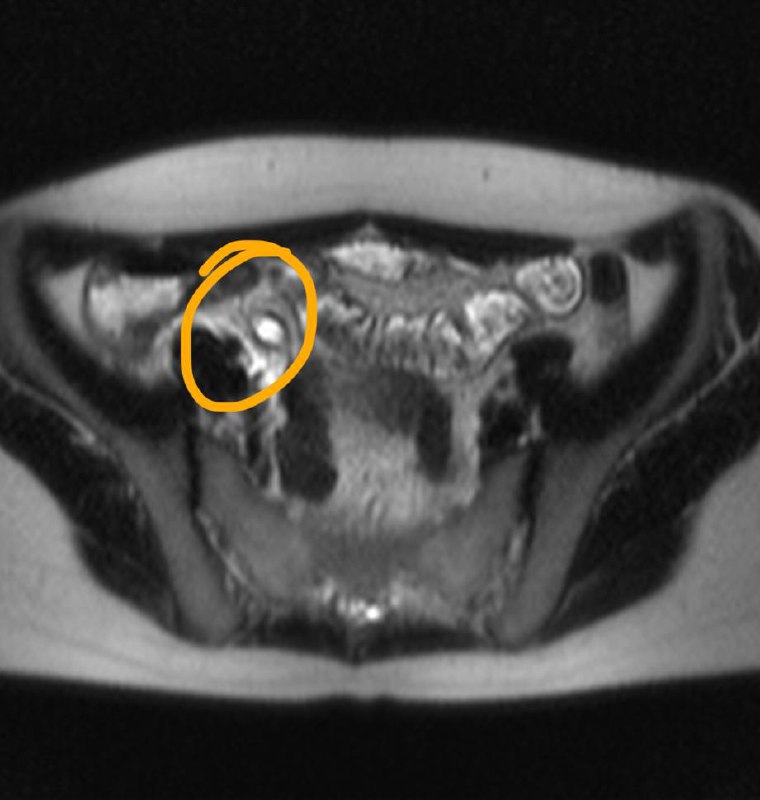

19 сен 2024

Когда рак простаты видно вот так, как здесь - исследование не вызывает отвращения, в отличие от случаев, когда приходится писать PIRADS-3..

Другое дело, что мы ж о пациентах заботимся, а не о себе, любимых, и каждый PIRADS-3 для пациента, все же, лучше, чем легко и непринуждённо обнаруживаемый, как в данном случае, PIRADS-5.

Пожелаем этому мужчине 75 лет успехов в лечении и минимума неприятных ощущений, которыми, неизбежно, такое лечение сопровождается.